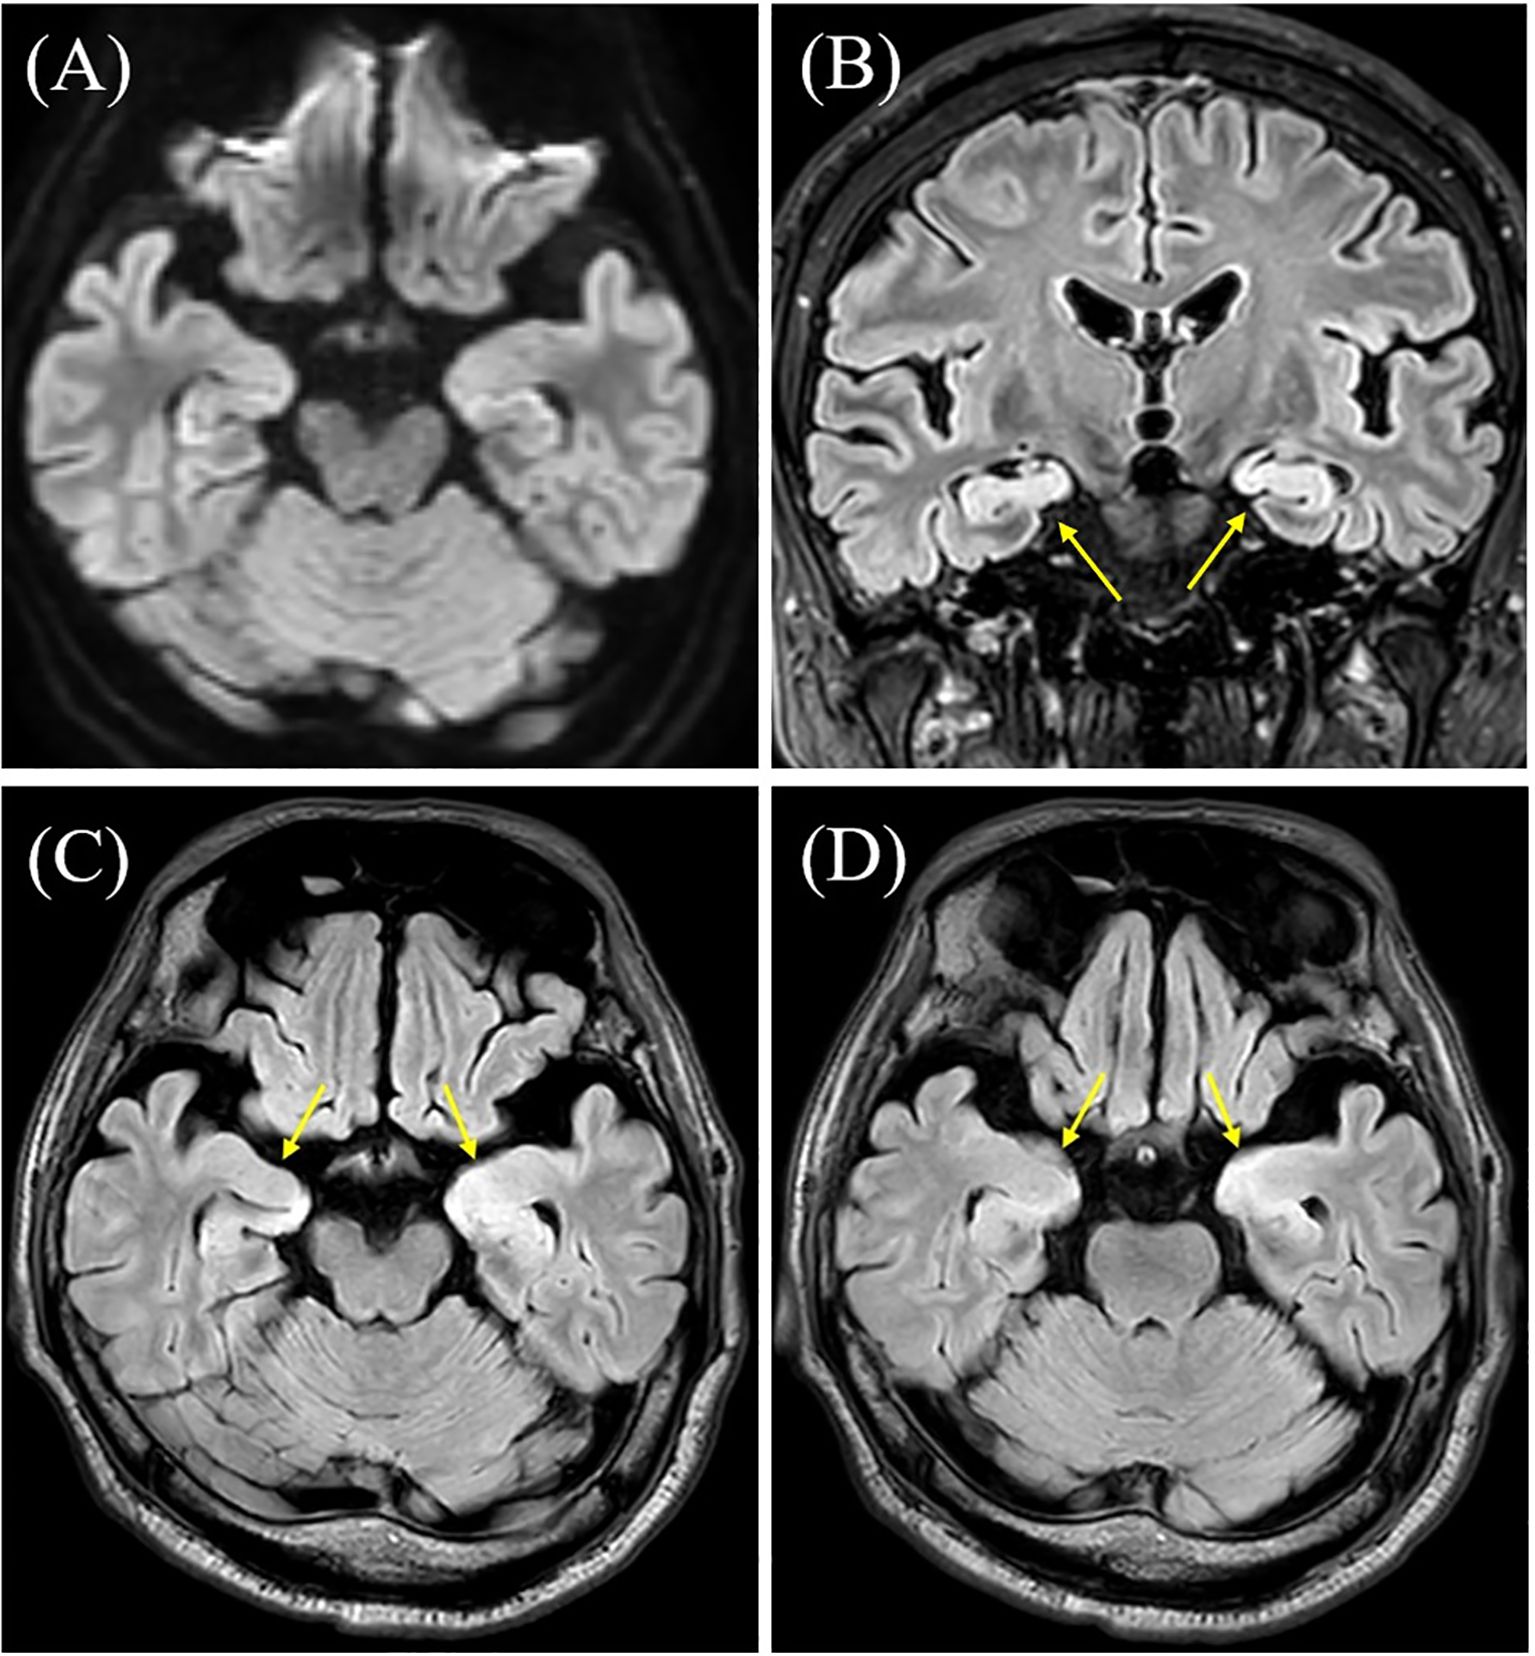

During the first week of hospitalization, he remained seizure-free. However, on day 8, his consciousness markedly declined, and he began experiencing recurrent, refractory seizures. A follow-up brain MRI revealed bilateral hyperintense lesions in the hippocampi on FLAIR imaging (Figure 2). Cerebrospinal fluid (CSF) analysis showed elevated cell counts (7/µl; reference <5/µl) and protein levels (50.2 mg/dL; reference 10–40 mg/dL), with normal glucose concentrations. On day 15, his respiratory status worsened, presenting with type 2 respiratory failure and requiring mechanical ventilation for two weeks.

Figure 2

Brain magnetic resonance imaging (MRI) results. (A) Diffusion-weighted brain MRI was unremarkable, including the hippocampus. (B–D) T2 fluid-attenuated inversion recovery (FLAIR) MRI showing hyperintensity in both hippocampi (arrows). Contrast-enhanced MRI was not performed.